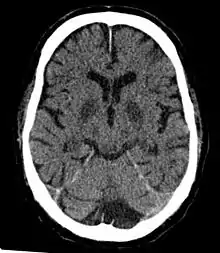

CT in a person after generalized hypoxia.

However, if blood flow cannot be increased or if doubled blood flow does not correct the problem, symptoms of cerebral hypoxia will begin to appear. Mild symptoms include difficulties with complex learning tasks and reductions in short-term memory. If oxygen deprivation continues, cognitive disturbances, and decreased motor control will result.[6] The skin may also appear bluish (cyanosis) and heart rate increases. Continued oxygen deprivation results in fainting, long-term loss of consciousness, coma, seizures, cessation of brain stem reflexes, and brain death.[7]